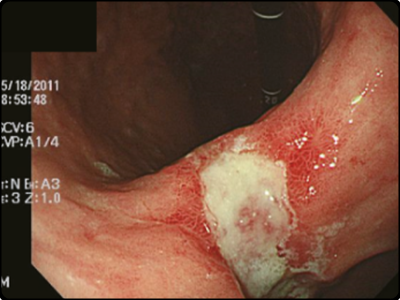

위암 초기증상: 갑작스러운 혈변 또는 대변색의 변화

위암이 진척되는 경우 복부에 덩어리가 느껴지기도 하고 변의 칼라가 흑색으로 나오거나 혈변을 볼 수 있습니다. 이러한 상황이 나타나면 건강에 문제가 생긴 것을 의심해봐야 합니다. 흑색변은 위 점막의 출혈 때문에 출현하는 증상중 한가지 입니다.

위의 출혈은 혈액이 위장에 머물러 있는 시간이 길어지면서 나타나는 증상입니다. 혈액이 장내 세균에 의해 분해가 됨으로써 검은색을 띄는 흑변 증상입니다. 때문에 장출혈과 위염증상 및 위암초기증상에서 출현하는 위출혈은 대변의 색으로 미리감치 구별을 할 수 있습니다.